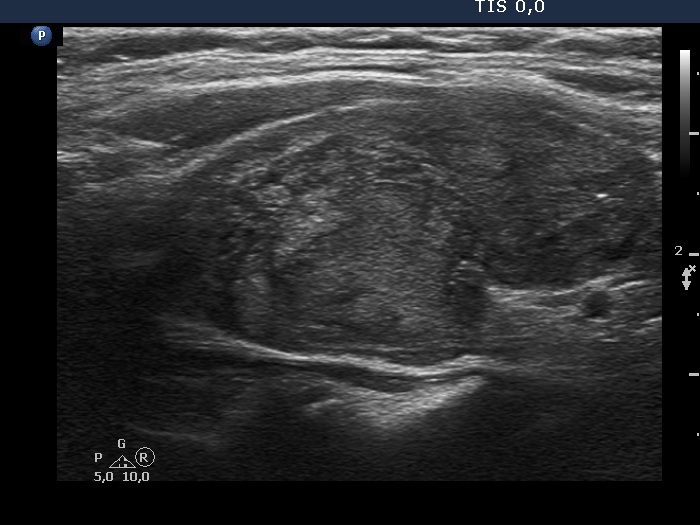

The echogenicity of the nodule - case 2067 (ultrasonographic picture 7)

Right lobe, longitudinal scan